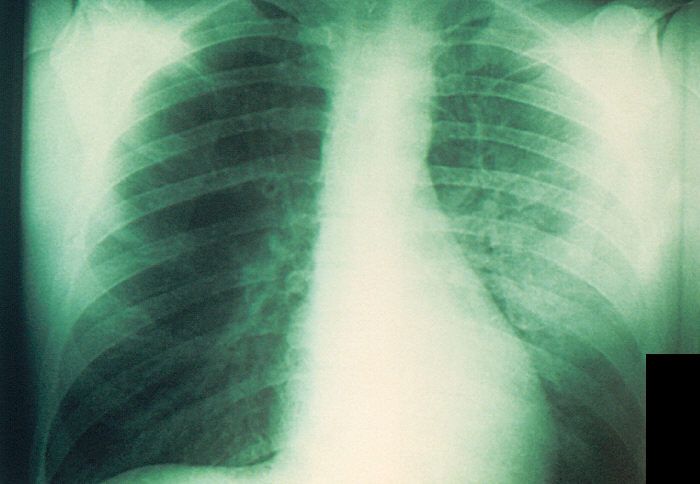

Röntgenbild einer mit Pest infizierten Lunge. (Symbolbild)

CDC, gemeinfrei